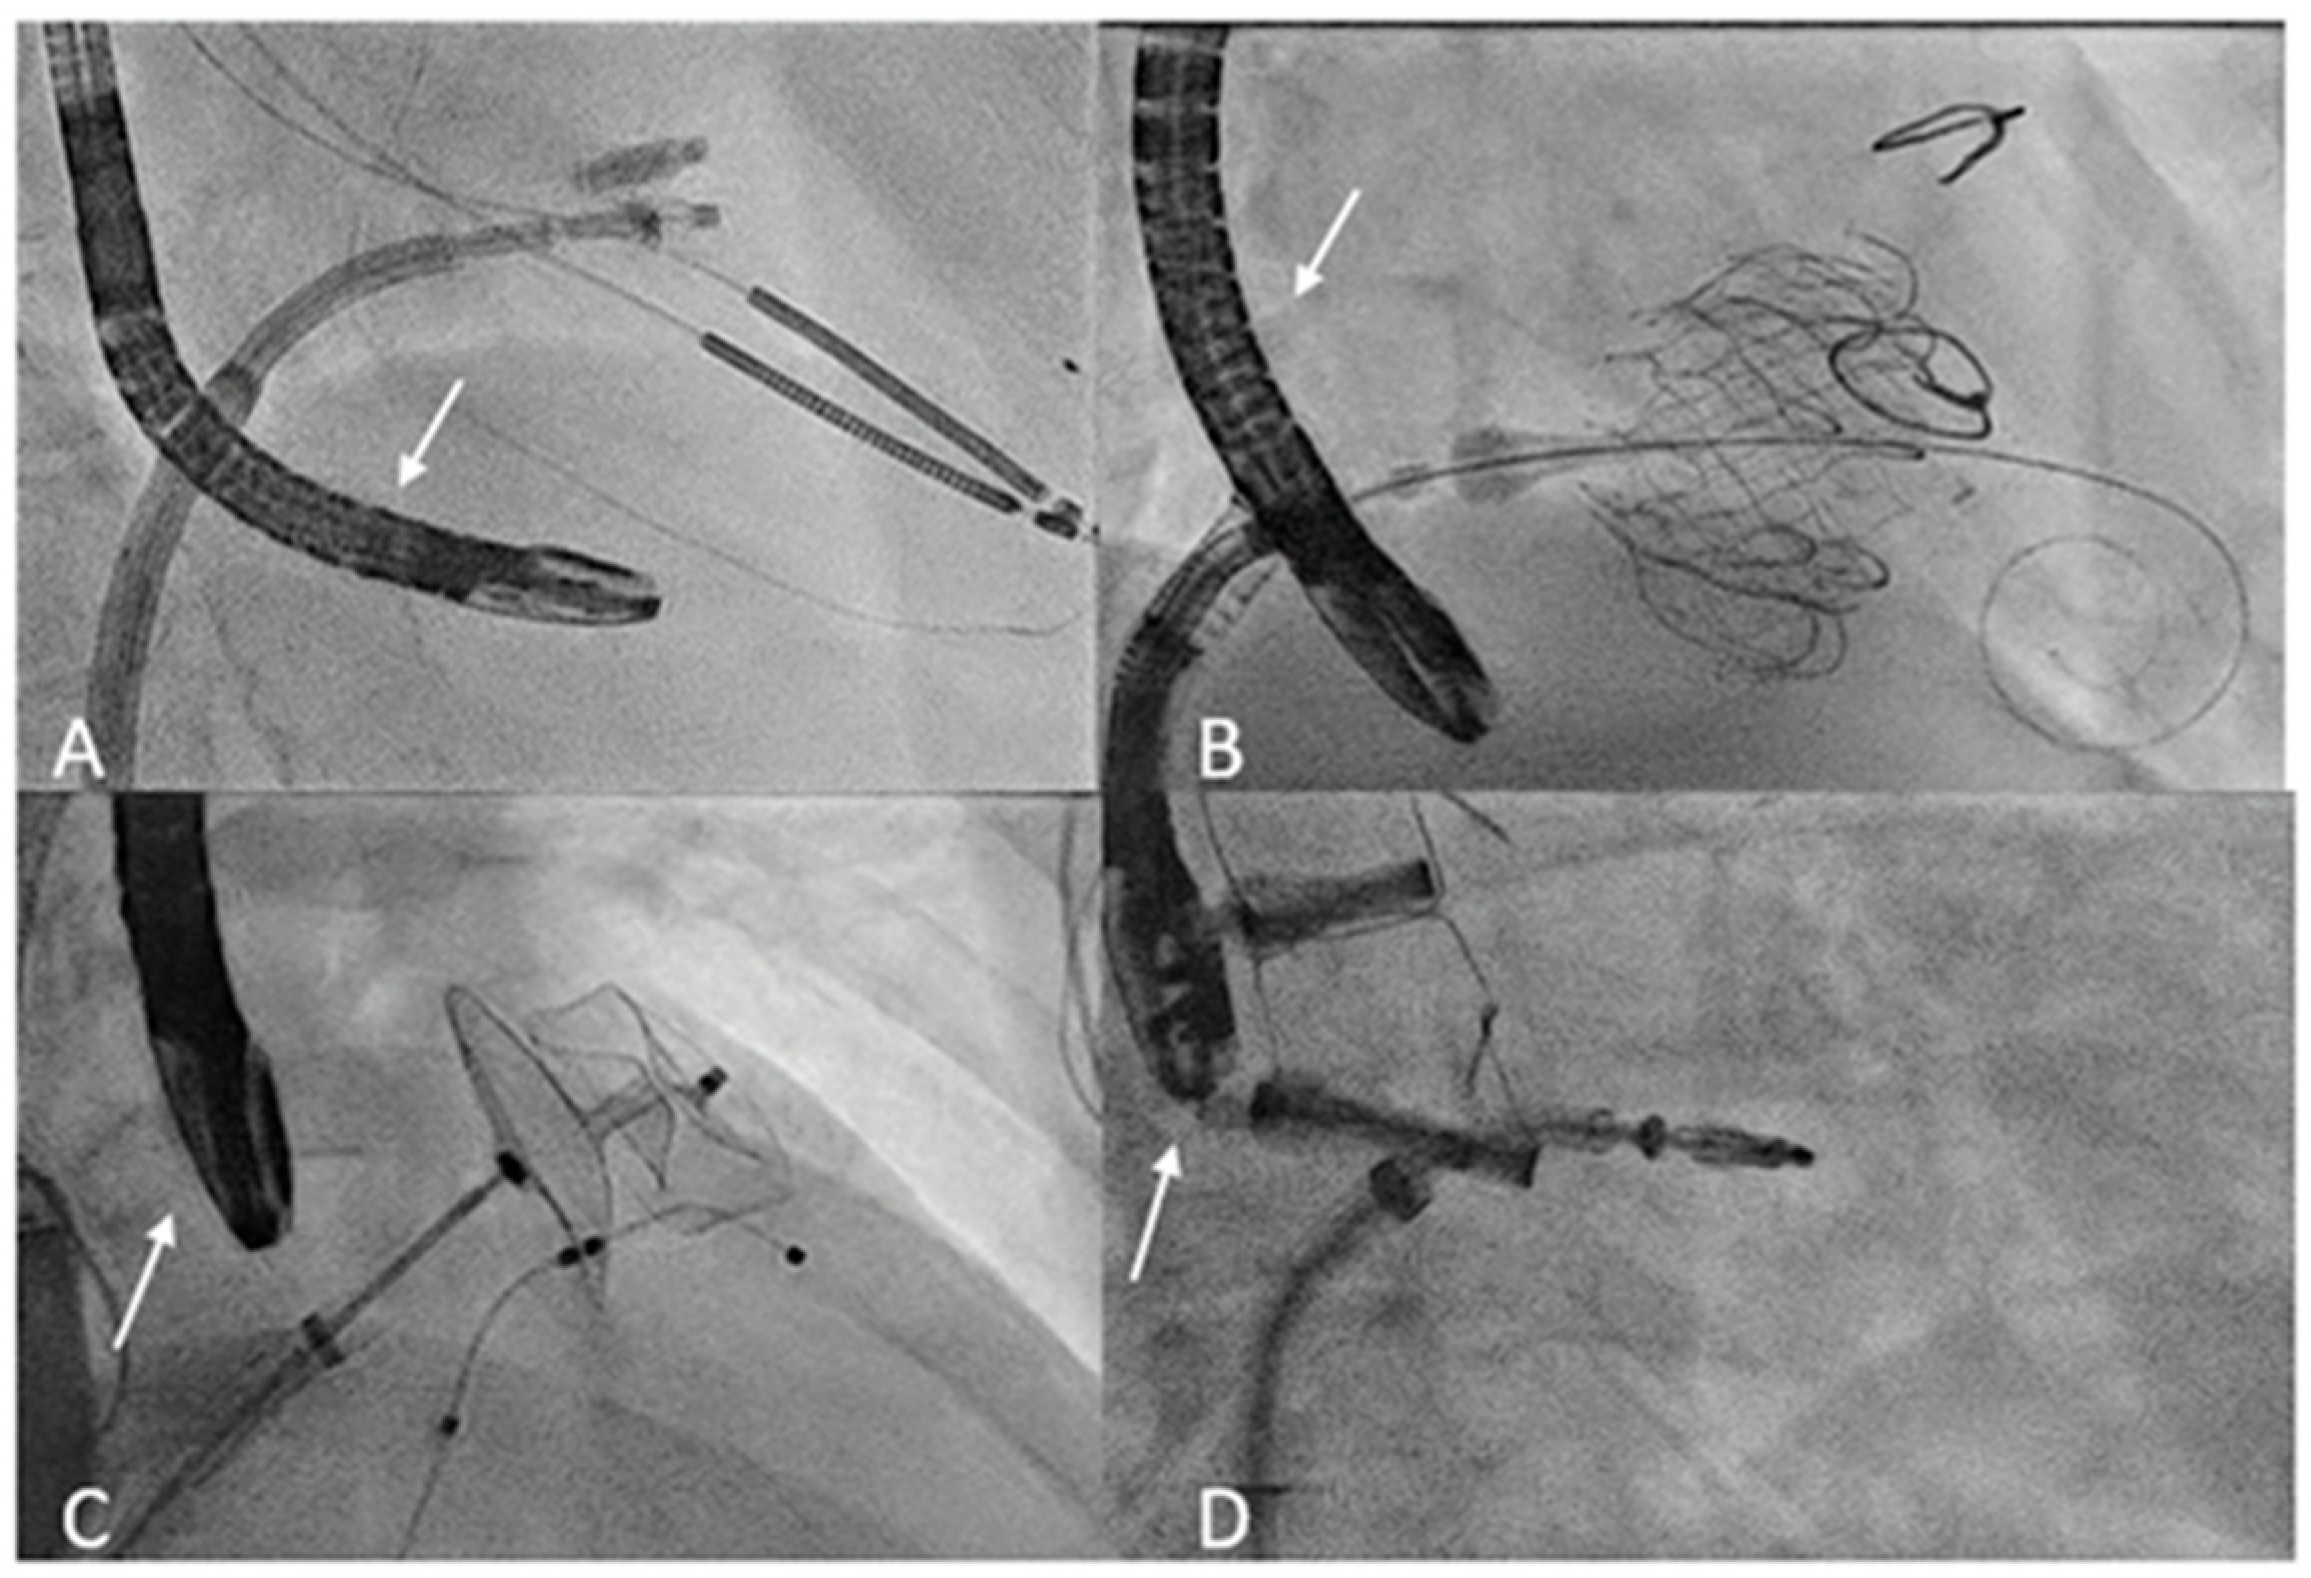

In interventional cardiology, TEE is often used for preoperative cardiac data evaluation, but procedure guidance and outcome assessment are also of crucial importance. In particular, TEE is an irreplaceable tool in terms of obtaining an optimal result. TEE used to guide catheter-based procedures involves constant manipulation of the probe during the interventions, in contrast to the TEE sequence utilized in an OR (Figure 1). In addition, patients undergoing percutaneous procedures tend to be sicker than patients undergoing surgery and may therefore be more susceptible to complications associated with intraprocedural TEE [42]. As such, there is a higher incidence of TEE-related problems in this scenario than in cardiac surgery populations [10].

Figure 1.

Transoesophageal probe position (arrow) during transcatheter interventions. (A) The fluoroscopy shows the transgastric probe position during T-TEER. (B) Deep esophageal view used during tricuspid valve replacement. (C) Mid esophageal probe position during LAA occlusion. (D) Mid esophageal probe position used during M-TEER. T-TEER: Tricuspid Transcatheter edge-to-edge repair; LAA: left atrial appendage; M-TEER: Mitral Transcatheter edge-to-edge repair.

Regarding procedure-related strategies, it is imperative that the imaging operator first examines the condition of the probe and checks for any wounds that may cause thermal damage and overheating. To guarantee probe flexibility and avoid esophageal tears caused by rigid tubes, the control system needs to be unlocked constantly [68]. After placement of the mouthguard, the probe should be gently introduced into the esophagus. Adequate probe lubrication can limit friction damage. If resistance is encountered, it is important to avoid forceful manipulation. In this case, the jaw-thrust technique may be helpful. Placement under laryngoscopic guidance also can help reduce hypopharynx and cervical esophagus damage [11,59]. Furthermore, a thorough assessment of vital signs and oxygen saturation can suggest the possibility of endotracheal tube displacement during esophageal intubation. Avoiding unnecessary manipulation after positioning the TEE probe can help to limit adverse effects. Moreover, anatomical markers of the probe position under fluoroscopy can help identify the correct placement and prevent over-probe manipulation when getting an acceptable alignment between the probe and the cardiac structures is difficult (Figure 1).